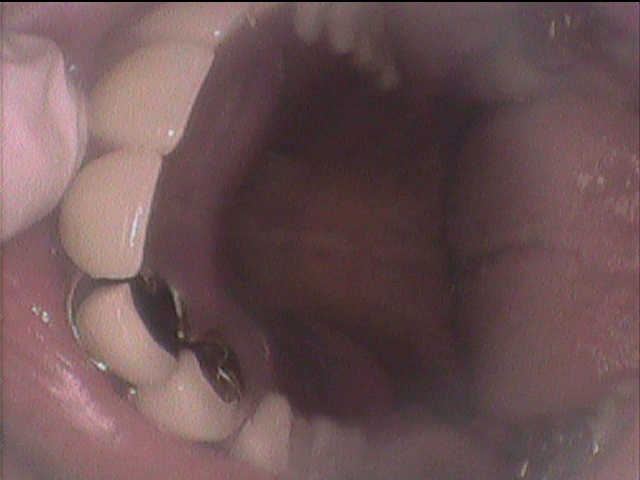

84歳女性のKさんは、下の顎が総入れ歯で、顎の状態が骨が少なく、

状態がよくないために、顎が入れ歯で痛くなりやすく、

コンフォート義歯を入れています。今回上の総入れ歯がやせてきてしまい、

新しく作製しました。上の顎の顎堤の状態は良好ではありませんが、

精密義歯で、いつでも顎の状態の変化に対応できる入れ歯を作製しました。

上の総入れ歯のコンフォート加工の症例です。 |